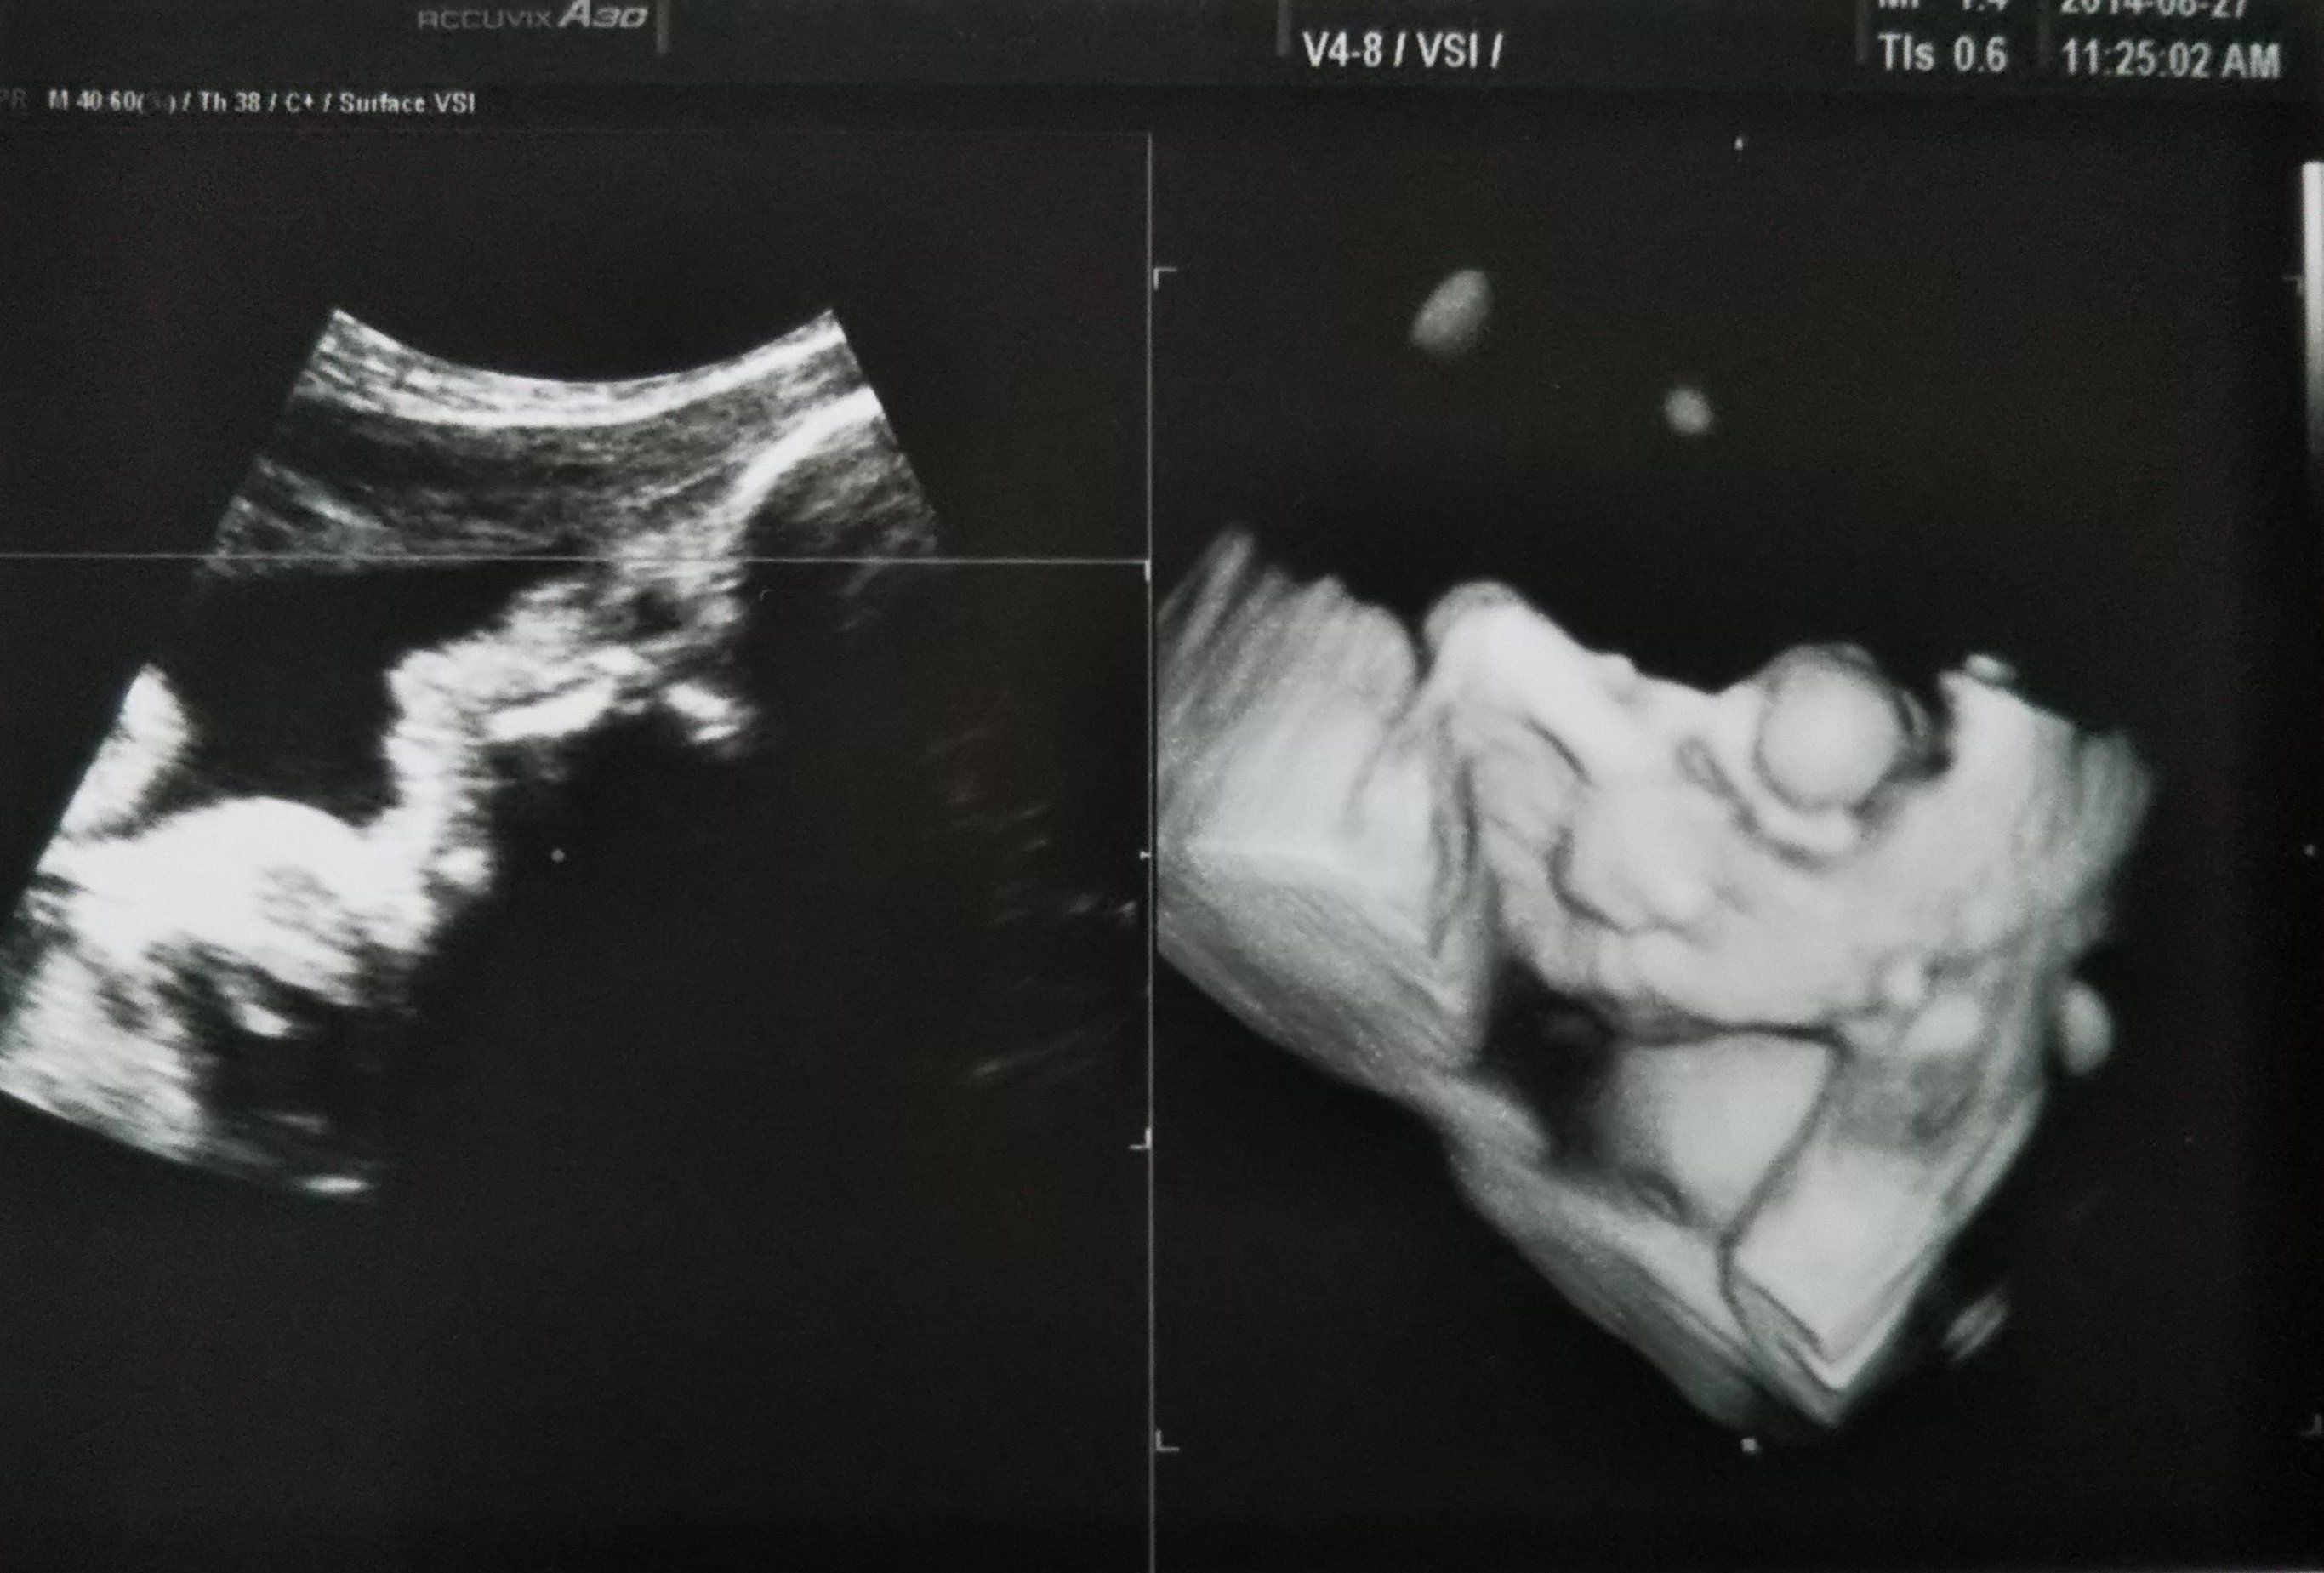

妊娠19週目のエコー写真 赤ちゃんの心室や膀胱の様子もエコーで確認できました。

妊娠19週目。性別がわかるかもしれないということで、主人も一緒について来た健診のときのエコー写真です。エコーを見せてもらって、先生から「心臓の部屋は4つ。膀胱におしっこも溜まっているから、腎臓にも異常なし。背骨もしっかりしていて体重等も標準。いい子です」と言っていただいてひと安心。帰りの車で主人に「先生、女の子って言っていたね」と言われてビックリ!聞き逃していた…。主人曰く「先生は女の子でまちがいないとも言っていたよ」とのこと。帰りに本屋さんに寄って、女の子の名前辞典を買いました。